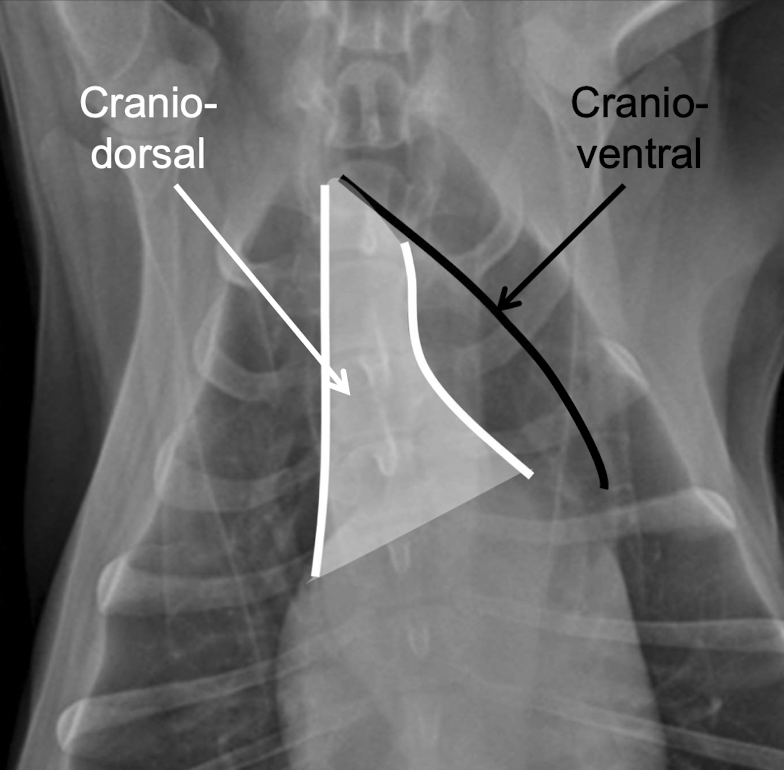

what is found in the cranioventral mediastinum

A

sternal lymph nodes

+/- thymus

what is found in the craniodorsal mediastinum

Great vessels

 Trachea

 Esophagus

 Cranial mediastinal lymph nodes